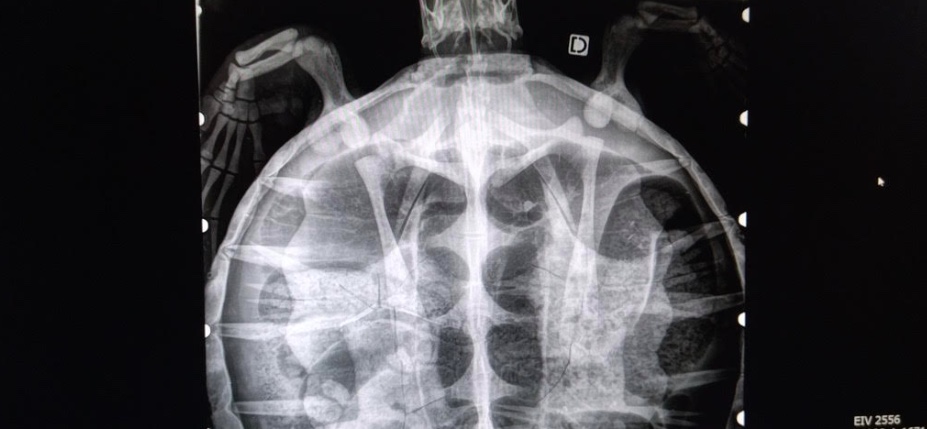

L’autopsie a confirmé de nombreuses fractures des os du plastron et de la dossière, dont une fracture ouverte du plastron.